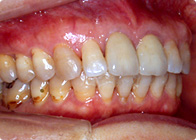

特に左側の歯並びが乱れています。上の犬歯の前後の歯肉に炎症があります。

左上もきれいに並びました。上の犬歯の歯肉の炎症も治りました。